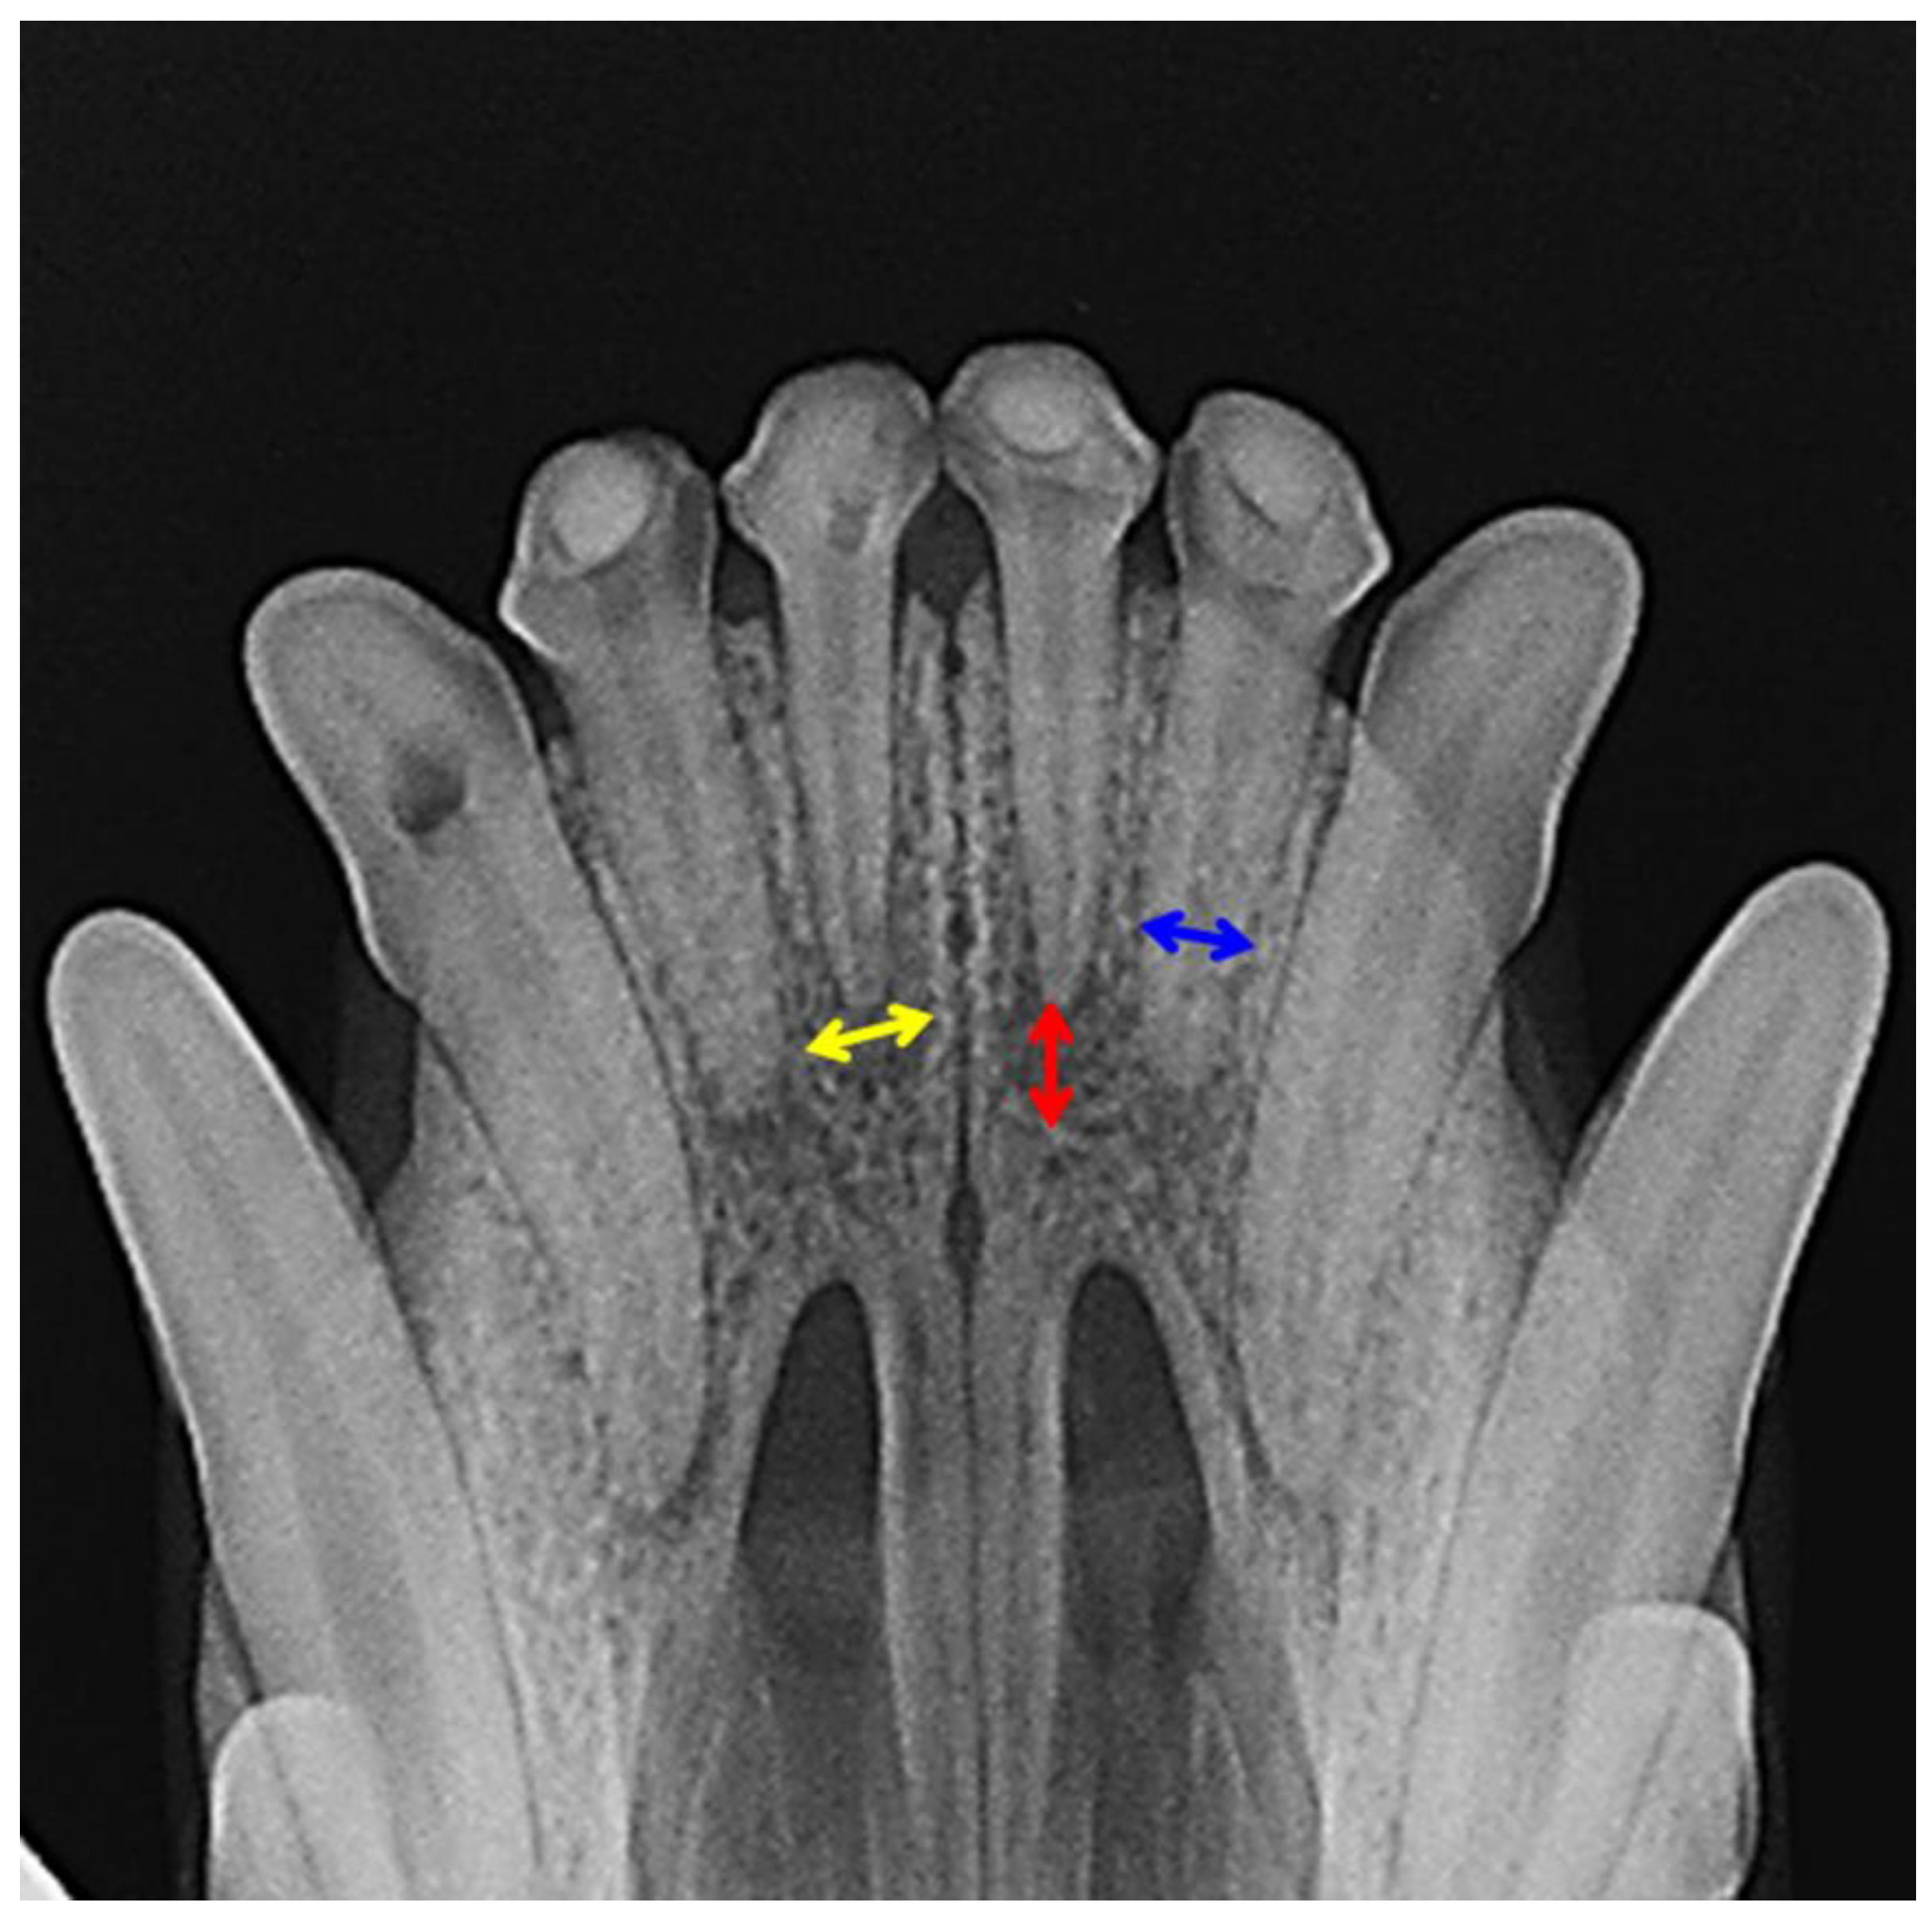

2.2.2. X-ray Analysis and Histology

| Horizontal radiolucency | Kruskal–Wallis test: p = 0.0412 | |||

| Vertical radiolucency | Kruskal–Wallis test: p =0.0152 | |||

| Conventional open | Conventional sealed | BDD sealed | Untouched | |

| Conventional open | 0.680 | 0.280 | 0.730 | |

| Conventional sealed | 0.664 | 0.940 | 0.170 | |

| BDD sealed | 0.167 | 0.862 | 0.030 | |

| Untouched | 0.899 | 0.297 | 0.039 | |

| Horizontal radiolucency | Kruskal–Wallis test: p = 0.0178 | |||